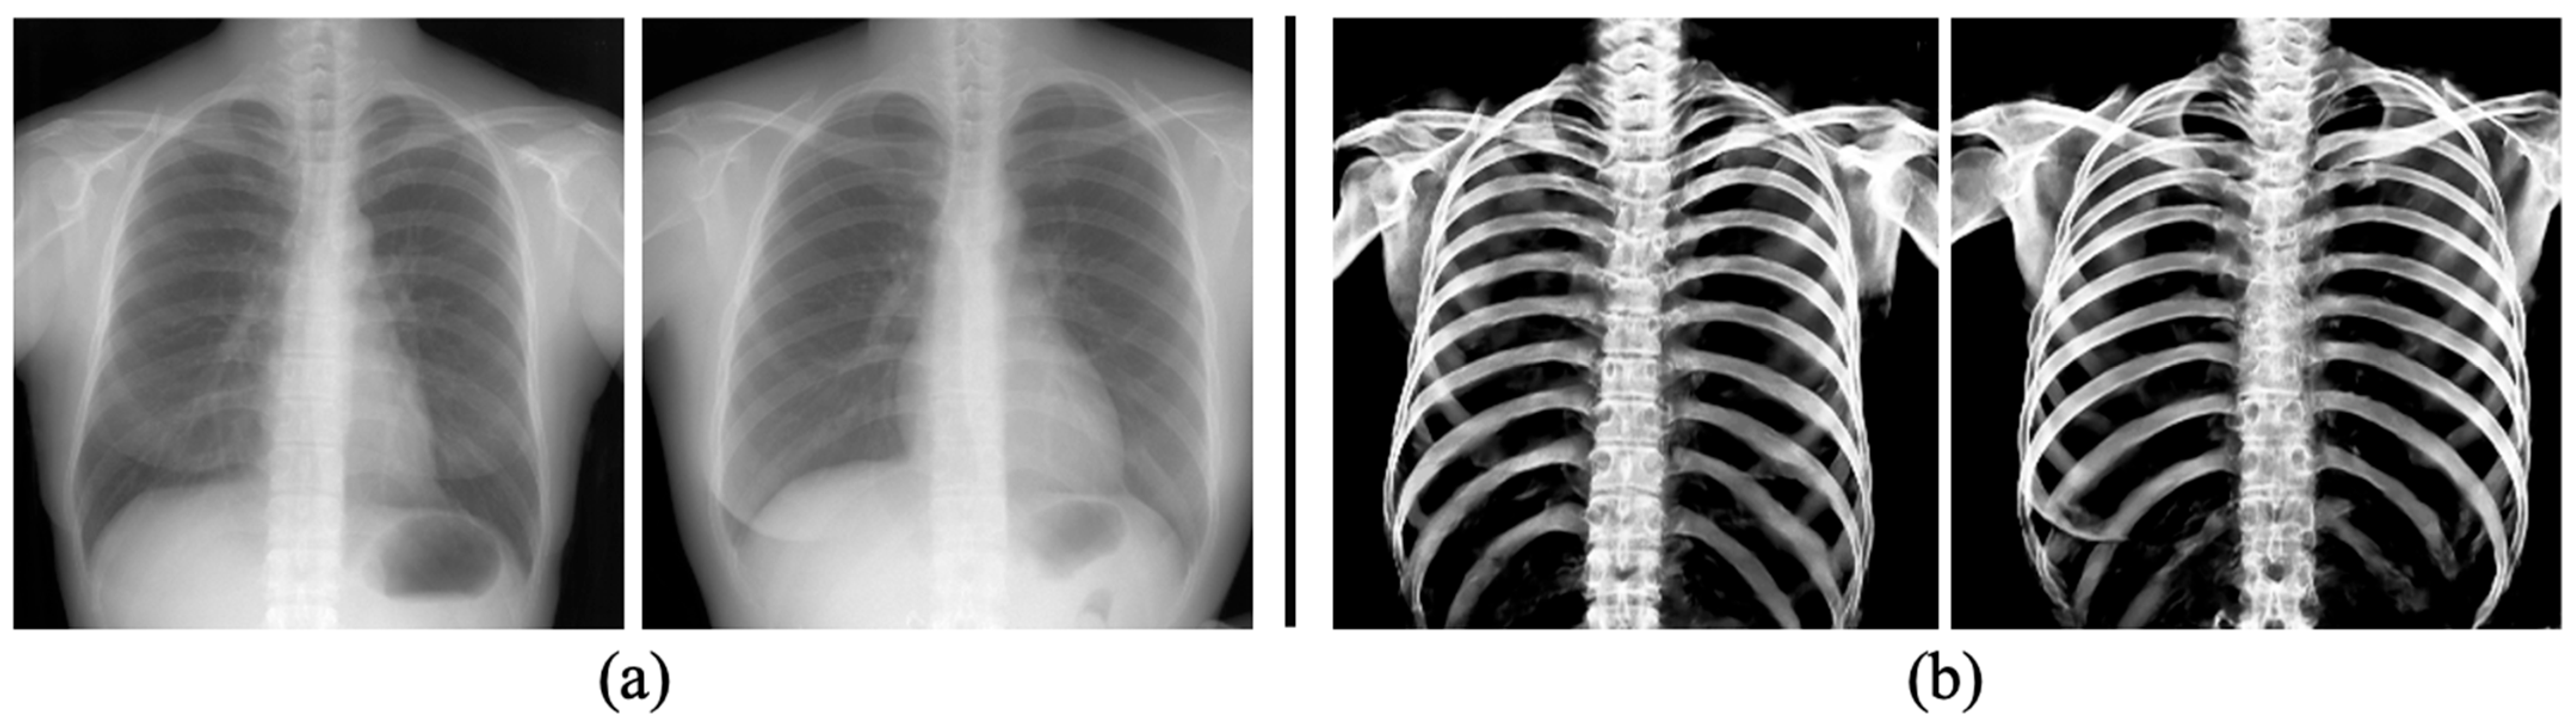

2.3. Pre-Processing: Producing Training Datasets from PMCT Images